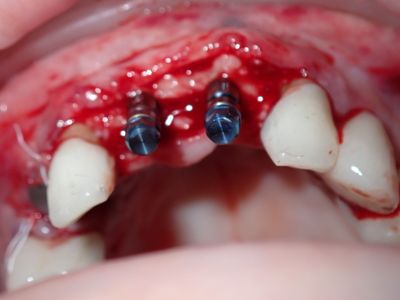

NSankhyan - immediate 13, impls 1121 and 25 with grafting

13 exo, loss of labial plate, implant placed buccal region grafted with sticky bone and collagen membrane soaked in prf fluid. 11/21 limited Labial-palatal width of bone, ridge split to 5mm, osteotomies prepared to about 2mm, remainder with densah drills, implants placed with ample bone, buccal grafted with same sticky bone. densah drills used for apical portion of 25 implant, soft bone, implant placed